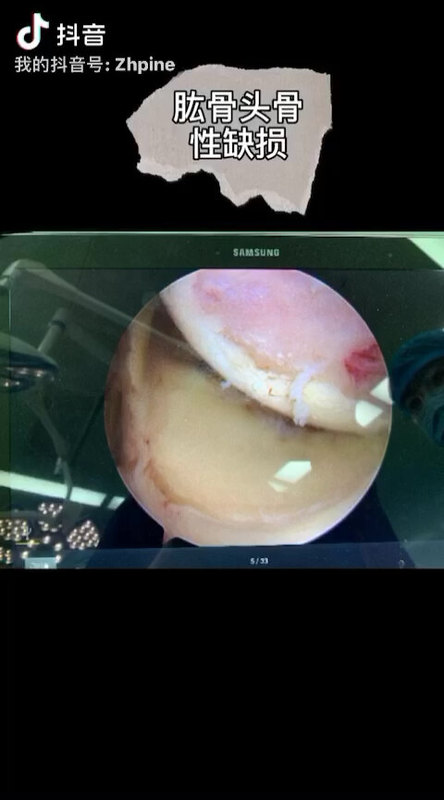

Hill-Sachs损伤

蔡明主任医师 上海市第十人民医院 骨科

5108人已读